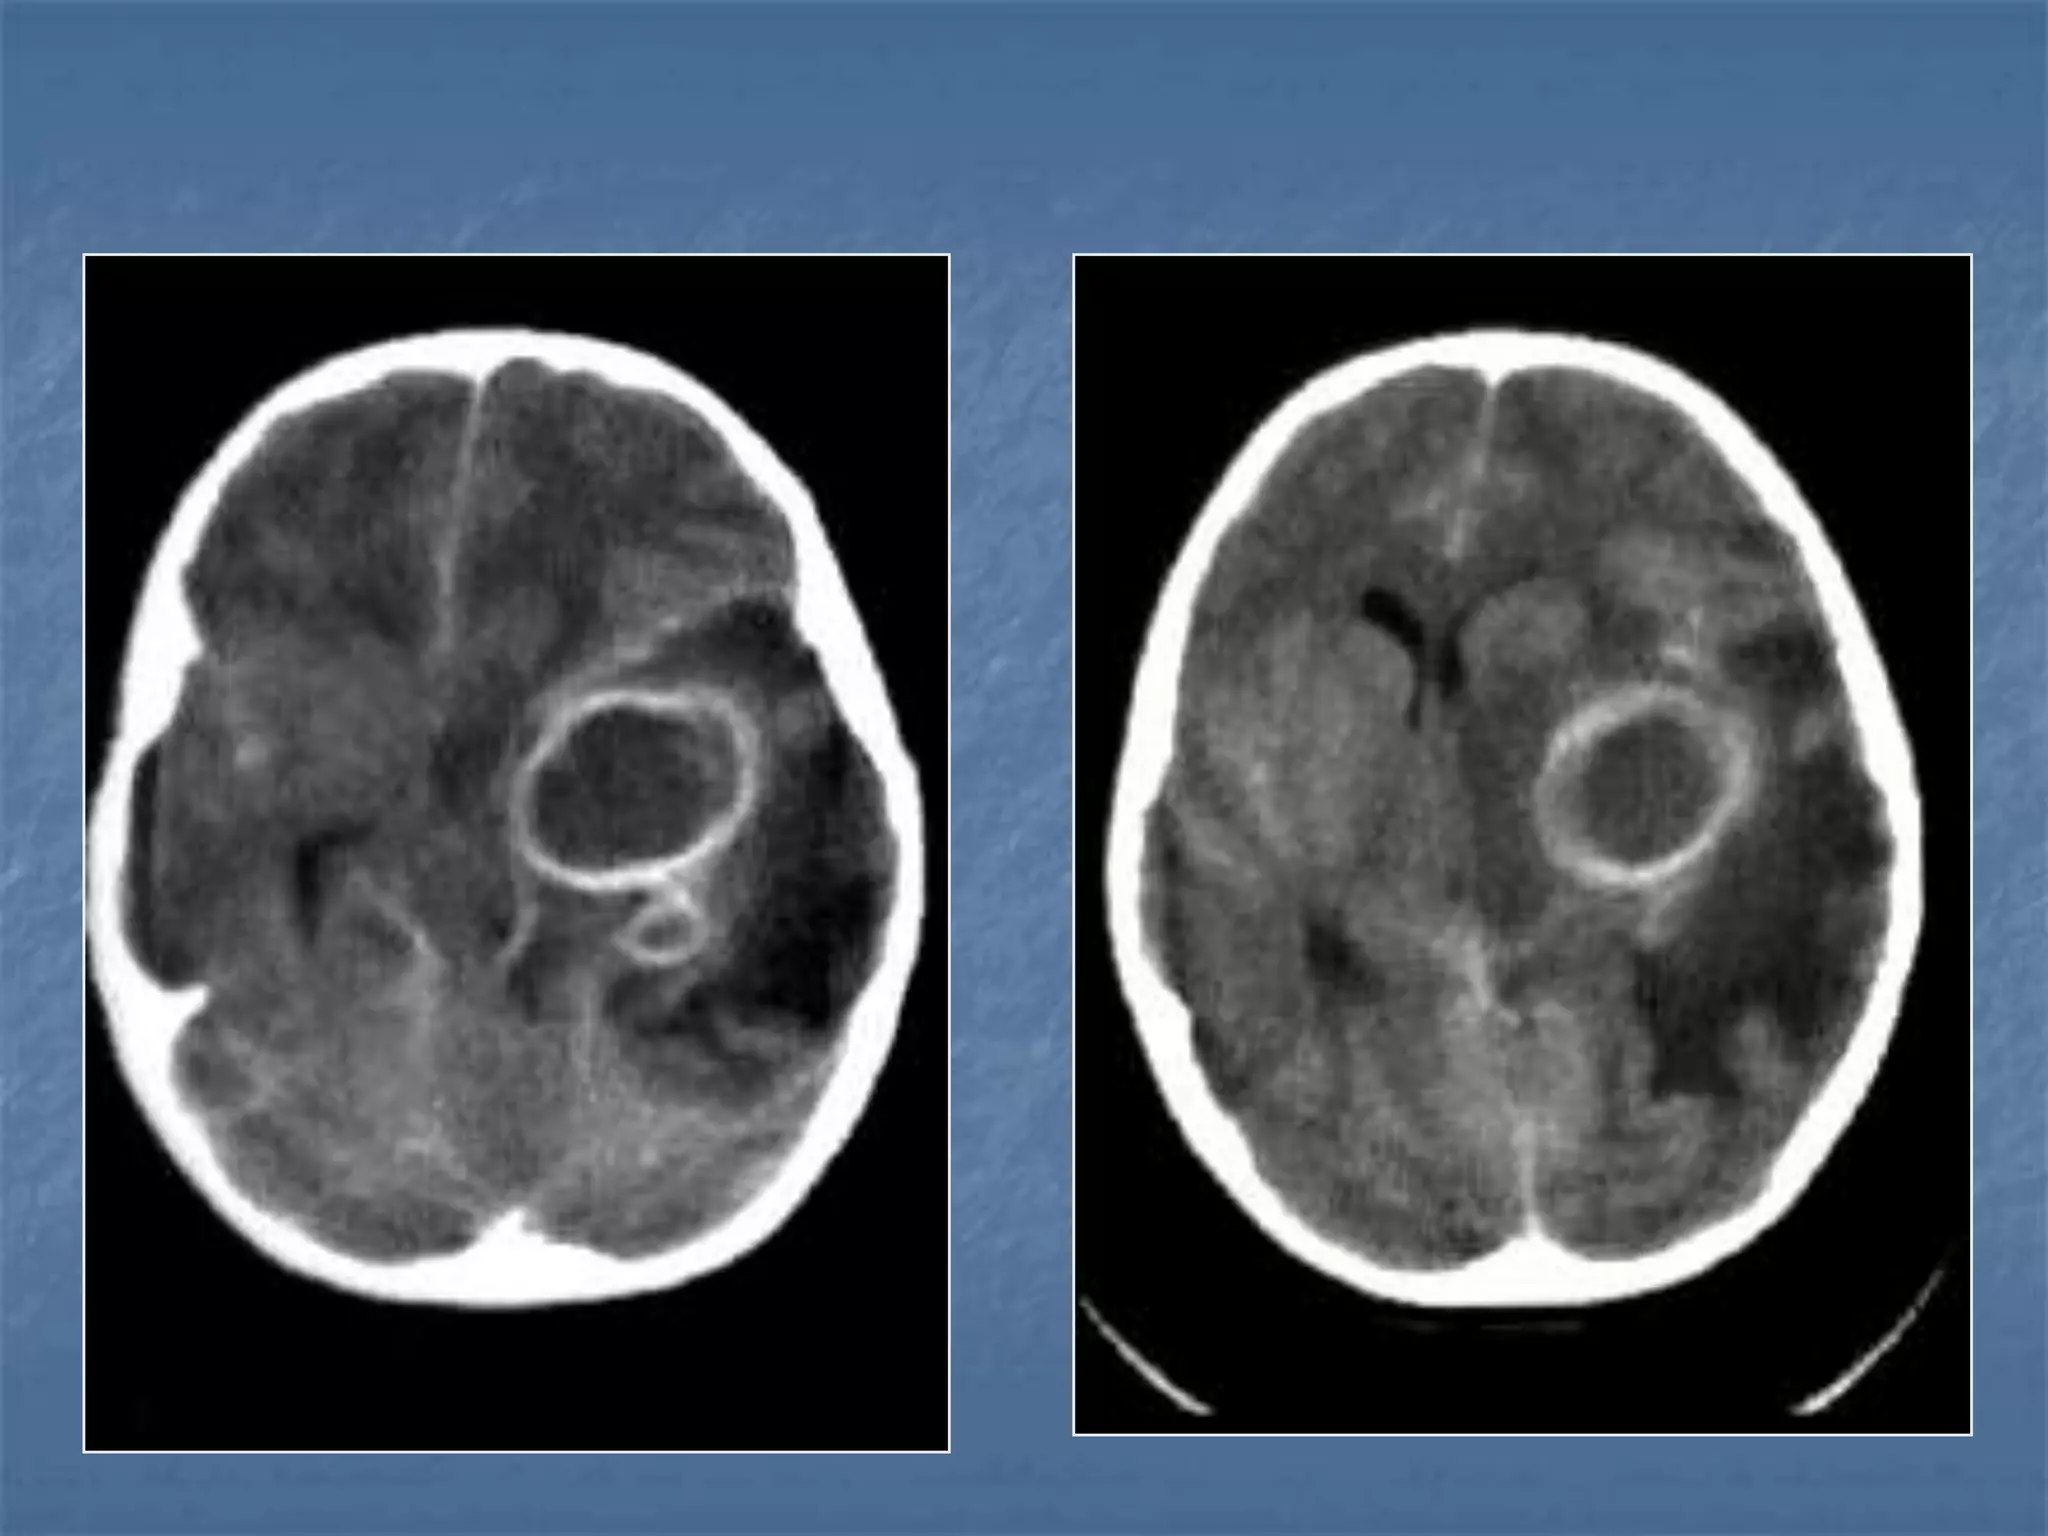

23 yr old male c/o fever and intense headache

 Ring enhancing lesions – granuloma /

abscess

 Calcifications

 Cerebritis

 Meningeal abnormalities

 Complications

Differential Diagnosis of Ring

Enhancing Lesions

 Granulomas

 Brain abscess

 Tumors – metastasis,

glioma

 Resolving hematoma

Encephalitis